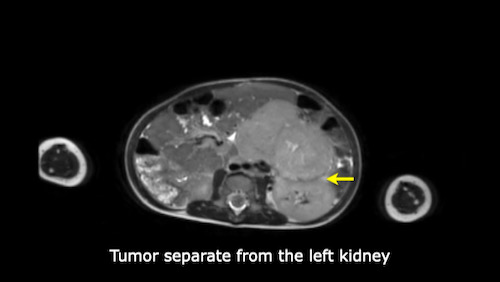

Mức độ lan rộng của khối u được đánh giá rõ ràng trên chuỗi xung TSE T2 weighted 3D theo mặt phẳng axial.

The left kidney is compressed and displaced caudally.

Có di căn hạch bạch huyết cạnh động mạch chủ (mũi tên vàng nhỏ).

Nguyên ủy của thân tạng và động mạch mạc treo tràng trên bị khối u bao quanh (đầu mũi tên).

Tĩnh mạch chủ dưới bị đẩy ra phía trước (mũi tên xanh).